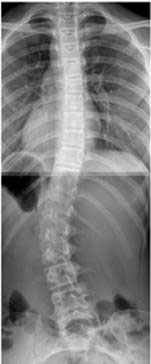

Skoliose

Skoliose ist eine dreidimensionale Fehlstellung der Wirbelsäule. Die dreidimensionale Skoliosebehandlung wurde von Katharina Schroth entwickelt und von ihrer Tochter Christa Lehnert-Schroth sowie ihrem Enkel, Herrn Dr. Weiß weiter entwickelt. Herr Dr. Weiß prägte die moderne konservative Skoliosebehandlung mittels "Schroth Best Practice®", einem Programm, welches Alltagsaktivitäten mit in das Übungsprogramm einbindet und innerhalb relativ kurzer Zeit erlernt werden kann. Darüber hinaus entwickelte er mit dem "Gensingen Brace" ein Korsett, welches gipsfrei gefertigt wird. Es zeichnet sich durch CAD (Nutzung von Datenbanken zur Korsettversorgung), Leichtbauweise und dreidimensionale Korrektur (insbesondere auch des Seitenprofils) aus.

Skoliose ist insgesamt eine eher seltene Erkrankung (Krümmungen von über 20° findet man lediglich bei 0,3-0,5 % der Bevölkerung). Daher gehört die Behandlung der Skoliose in die Hände von Experten. Wir bieten ihnen am Standort Zell eine hochqualitative und umfassende Versorgung an.

Darüber hinaus befindet sich in Zell-Barl eine radiologische Praxis (MVZ Mittelmosel). Hier ist eine ehemalige Mitarbeiterin von Herrn Dr. Weiß (vertraut mit der besonderen Röntgeneinstelltechnik zur Verminderung der Strahlenexposition bei Wirbelsäulenganzaufnahmen) tätig.